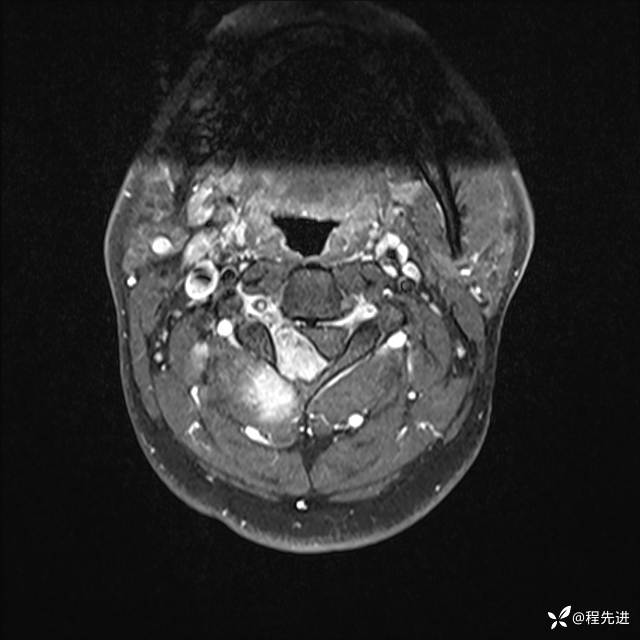

MRI平扫+增强:

T1增强: